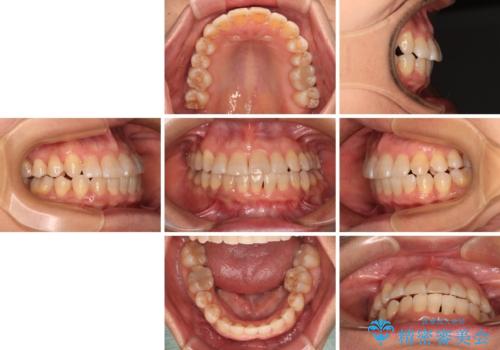

下顎の正中を歯1本分ずらした位置とすることで、外見上の骨格的なずれをカバーするように計画しました。

クロスバイトを改善したことで、前歯の負担が軽減し、安定して噛めるようになりました。